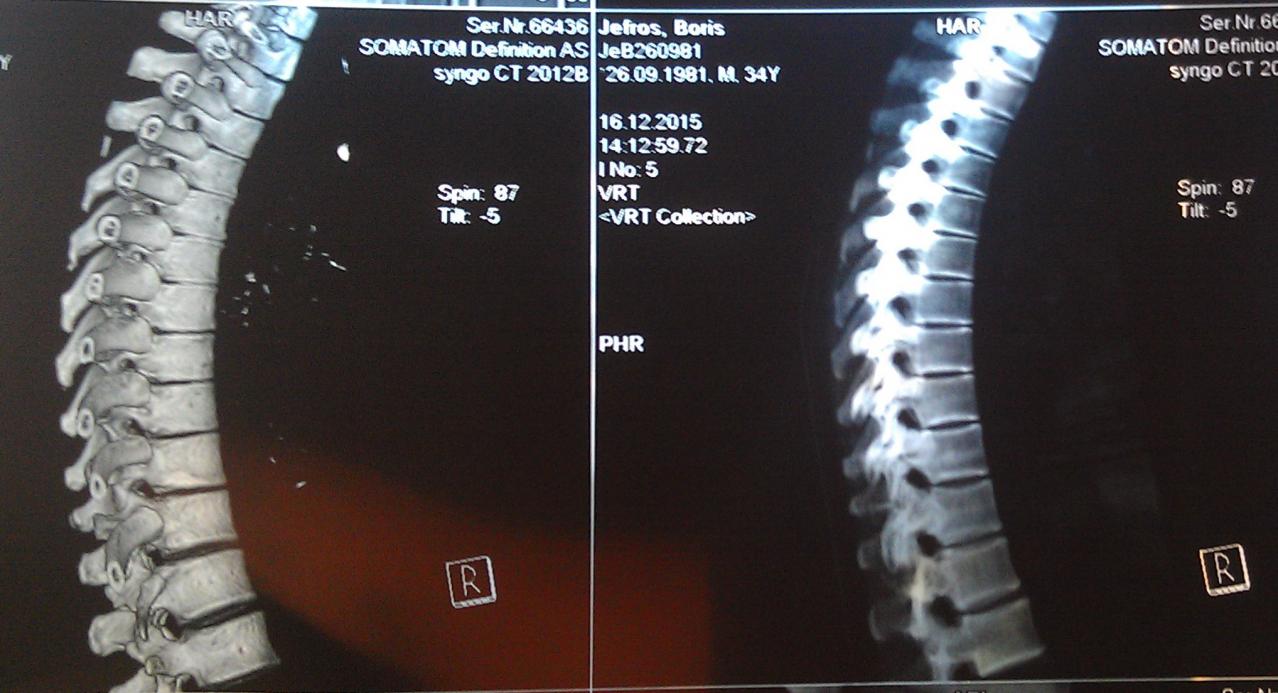

А достаточно ли плохих ревмопроб и компьютерной томограммы, где виден кифоз - чтобы поставить диагноз "болезнь Бехтерева"?

Вот моя компьютерная томограмма позвоночника.

Нажмите на изображение для увеличения

Название: 1 - компьютерная томограмма позвоночник, грудной отдел.jpg

Просмотров: 1600

Размер:	83.2 Кб

ID:	1182Нажмите на изображение для увеличения

Название: 3 - компьютерная томограмма на болезнь Бехтерева.jpg

Просмотров: 1596

Размер:	92.7 Кб

ID:	1184Нажмите на изображение для увеличения

Название: 4 - Снимок позвоночника.jpg

Просмотров: 1571

Размер:	85.8 Кб

ID:	1185Нажмите на изображение для увеличения

Название: 5 - позвоночник при остеохондрозе.jpg

Просмотров: 1628

Размер:	91.0 Кб

ID:	1186Нажмите на изображение для увеличения

Название: 2 - компьютерная томограмма позвоночник.jpg

Просмотров: 1610

Размер:	95.5 Кб

ID:	1183

Судя по снимкам ярко выраженный кифоз, отсюда и сдавливание легких Плохо видно, вроде срастания позвонков нет и это очень хорошо, На данном этапе желательно следить за своим прямохождением-прямосидением и упражнениями способствующими этому.Не ходить к костоломам, ну вроде как потянем-растянем-подстукнем и тд.